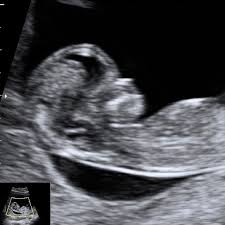

A blood sample of the expecting mother is sufficient for the examination. However I had a panorama test at 12 weeks and everything came back good. Non-invasive prenatal testing is a new highly accurate screen for specific chromosome abnormalities like trisomy 21 Down syndrome trisomy 18 Edwards syndrome trisomy 13 Patau syndrome and monosomy X Turner syndrome.

NON-INVASIVE PRENATAL TEST NIPT The test identifies more than 99 of fetuses with trisomy 21 which causes Down Syndrome. Down syndrome and other chromosomal abnormalities such as trisomy 13 or trisomy 18 are very likely to be detected with their help.